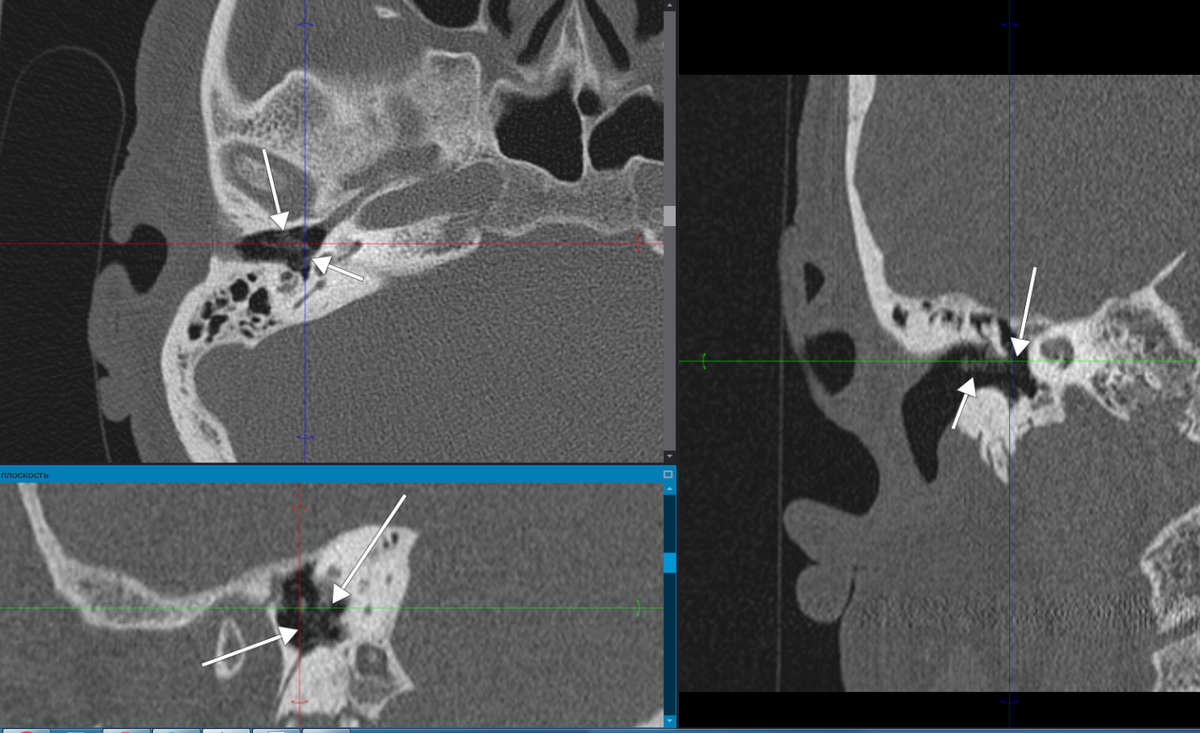

Рис.1. Изображение пристеночных наложений.

Рис.3. Наложение патологического субстрата вокруг рукоятки молоточка с распространением на область среднего уха.